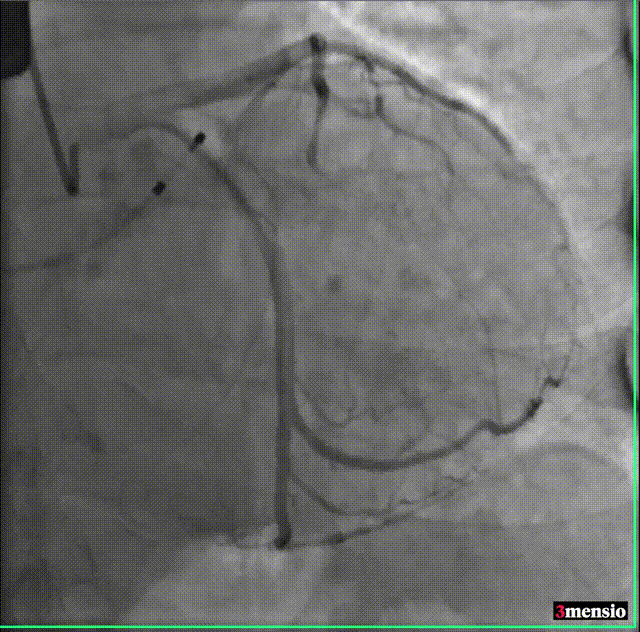

术前冠脉造影

主动脉根部造影